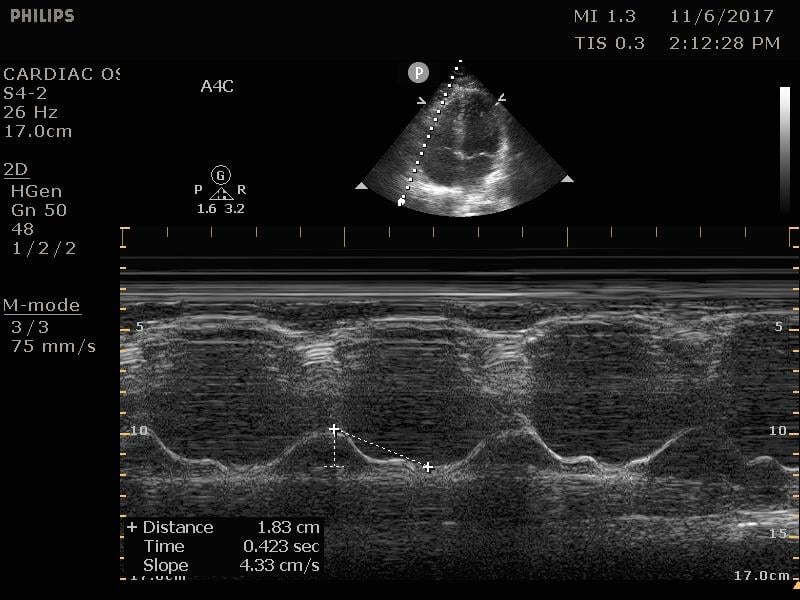

TAPSE

The tricuspid annular plane systolic excursion (TAPSE) is a measurement of the right-sided systolic function. In the emergency department, this is most commonly employed to assess for signs of right heart strain in a patient with suspected or confirmed pulmonary embolism. This is a good prognostic test, although insufficiently sensitive for the diagnosis of any pulmonary embolism.16 On the apical four chamber view, place the m-mode cursor over the lateral annulus of the tricuspid valve. This provides a waveform that can be measured from peak to trough. Measurements less than 16 mm are considered indicative of poor right ventricular function and correlate with increased mortality.17

Figure 13. Normal TAPSE as measured on M-mode

- A TAPSE can be measured to evaluate the right heart systolic function. A TAPSE <16mm signifies increased mortality.17